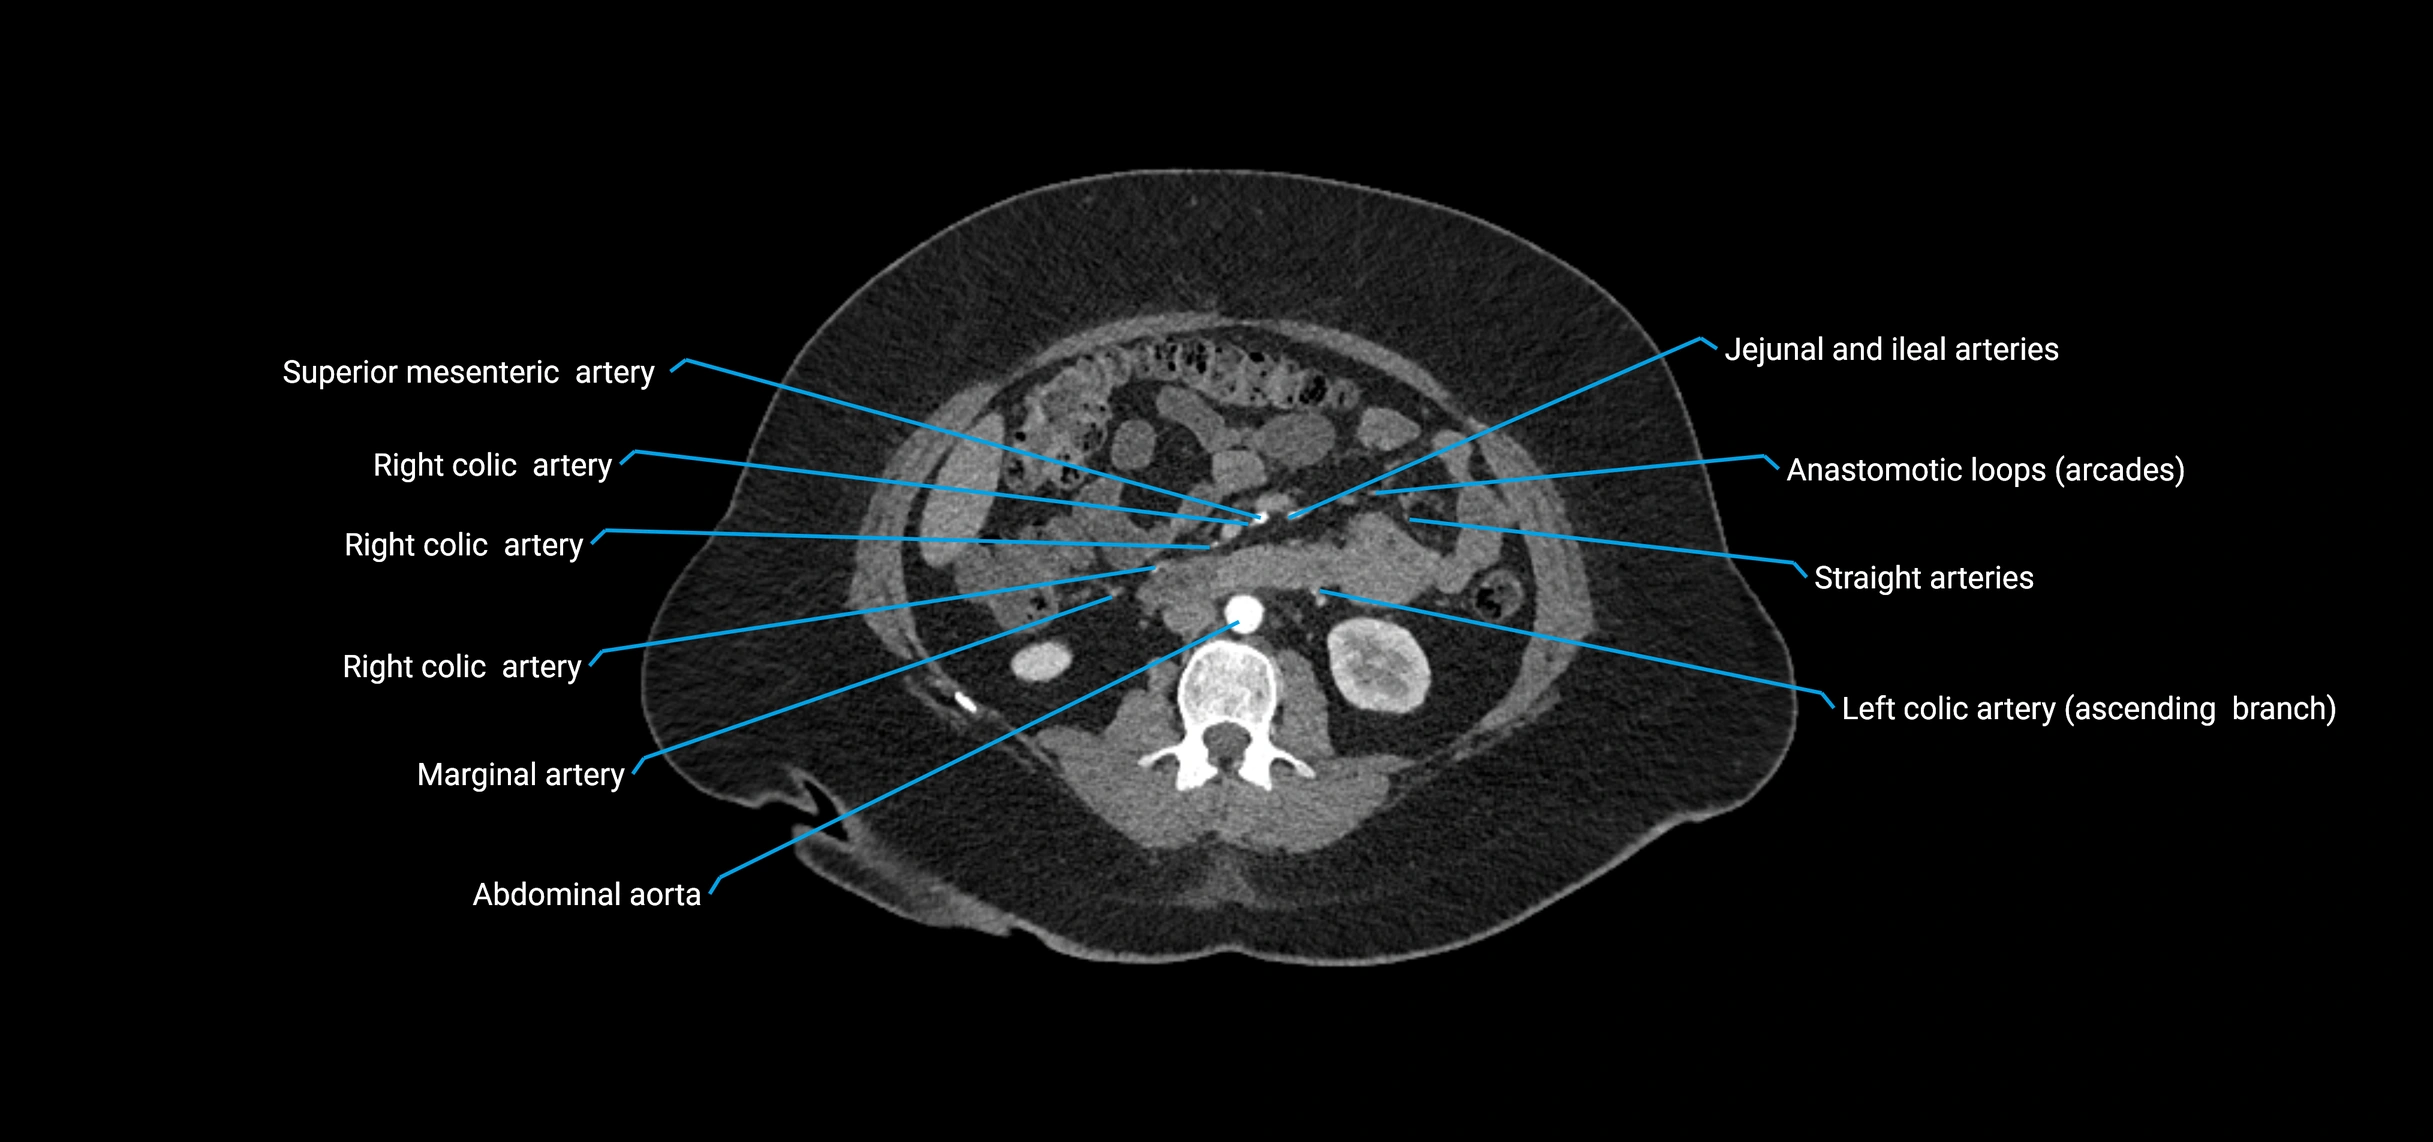

Contrast-enhanced CT (CTA):

• Gold standard for abdominal aortic imaging

• Provides excellent detail of lumen, wall, aneurysm, thrombus, and branch vessels

• Multiplanar and 3D reconstructions help in aneurysm measurement, stent graft planning, and dissection evaluation

• Detects acute rupture, traumatic injury, or occlusion with high sensitivity